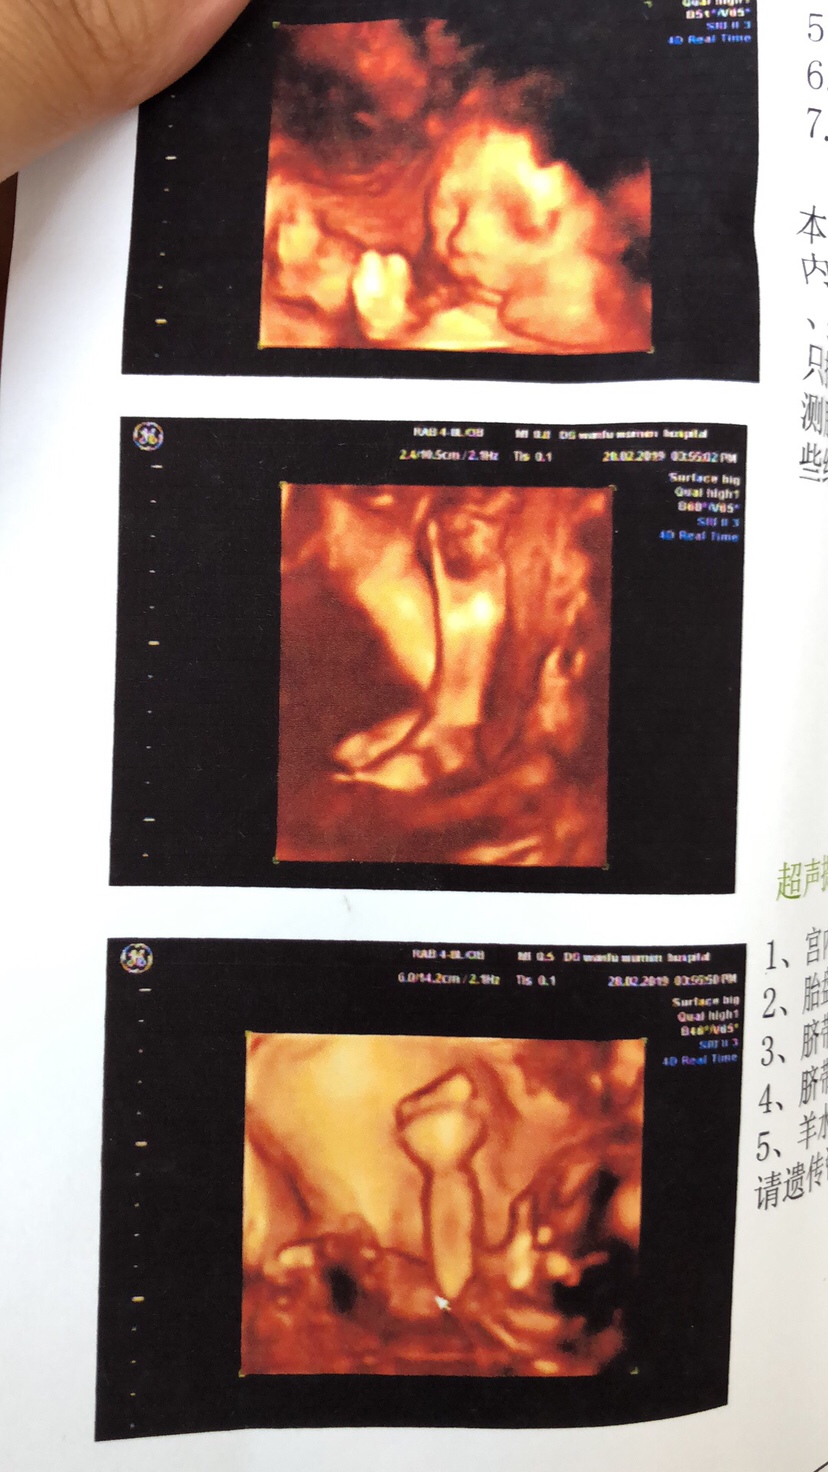

孕22周+0天

真的,好像是男宝宝呀